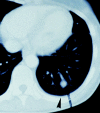

Dendritic cells (DCs) are considered to be promising adjuvants for inducing immunity to cancer. We used mature, monocyte-derived DCs to elicit resistance to malignant melanoma. The DCs were pulsed with Mage-3A1 tumor peptide and a recall antigen, tetanus toxoid or tuberculin. 11 far advanced stage IV melanoma patients, who were progressive despite standard chemotherapy, received five DC vaccinations at 14-d intervals VSports手机版. The first three vaccinations were administered into the skin, 3 x 10(6) DCs each subcutaneously and intradermally, followed by two intravenous injections of 6 x 10(6) and 12 x 10(6) DCs, respectively. Only minor (less than or equal to grade II) side effects were observed. Immunity to the recall antigen was boosted. Significant expansions of Mage-3A1-specific CD8(+) cytotoxic T lymphocyte (CTL) precursors were induced in 8/11 patients. Curiously, these immune responses often declined after the intravenous vaccinations. Regressions of individual metastases (skin, lymph node, lung, and liver) were evident in 6/11 patients. Resolution of skin metastases in two of the patients was accompanied by erythema and CD8(+) T cell infiltration, whereas nonregressing lesions lacked CD8(+) T cells as well as Mage-3 mRNA expression. This study proves the principle that DC "vaccines" can frequently expand tumor-specific CTLs and elicit regressions even in advanced cancer and, in addition, provides evidence for an active CD8(+) CTL-tumor cell interaction in situ as well as escape by lack of tumor antigen expression. .